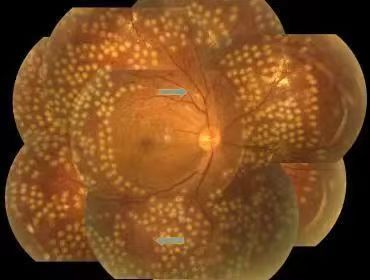

不同程度的糖尿病視網膜病變

此外需注意的是,對于女性糖尿病患者,妊娠會加速糖尿病性視網膜病變(DR)的發生和發展,需要定期復查,并在醫生指導下進行激光光凝術等對應治療。

視網膜激光光凝:采用激光的熱凝效用,在局部出血部位和(或)無灌注區形成凝固激光斑,達到止血、預防再出血的效果。該治療為增殖期病變的首選治療方式,較早實行全視網膜光凝能有效預防失明,且價格低廉,效果較好。

激光光凝治療

視網膜激光光凝術是治療糖尿病性視網膜病變(DR)的重要手段,分為全視網膜激光光凝(PRP)、黃斑格柵樣激光光凝等。激光光凝術是高危增殖性糖尿病性視網膜病變(DR)患者及某些嚴重非增殖性患者的主要治療方式。

激光治療旨在減少視力進一步下降的危險,盡量保護視功能。高危增殖性糖尿病性視網膜病變患者應迅速施行全視網膜激光光凝治療。約50%的重度非增殖性糖尿病性視網膜病變患者在1年內可進展為增殖性糖尿病性視網膜病,15%進展為高危增殖性糖尿病性視網膜病,若病情進展應考慮行全視網膜激光光凝治療。

在激光之前,若已經出現明顯的黃斑水腫,應先治療黃斑水腫,因大面積的視網膜光凝,會導致黃斑水腫的進一步加重。以前,臨床通常采用口服藥物或者先對黃斑進行光凝的處理,近年來,更多采用抑制血管內皮生長因子的方法處理黃斑水腫問題。

全視網膜激光光凝術后

在結束激光治療時,很多患者會表示視力反而不如治療前。這種現象,實際是激光過程中,對視網膜產生了彌漫性的光漂白作用,通常半小時左右的時間就可以恢復,不需要特殊處理。總體來說,激光治療是安全且并不會導致失明的。